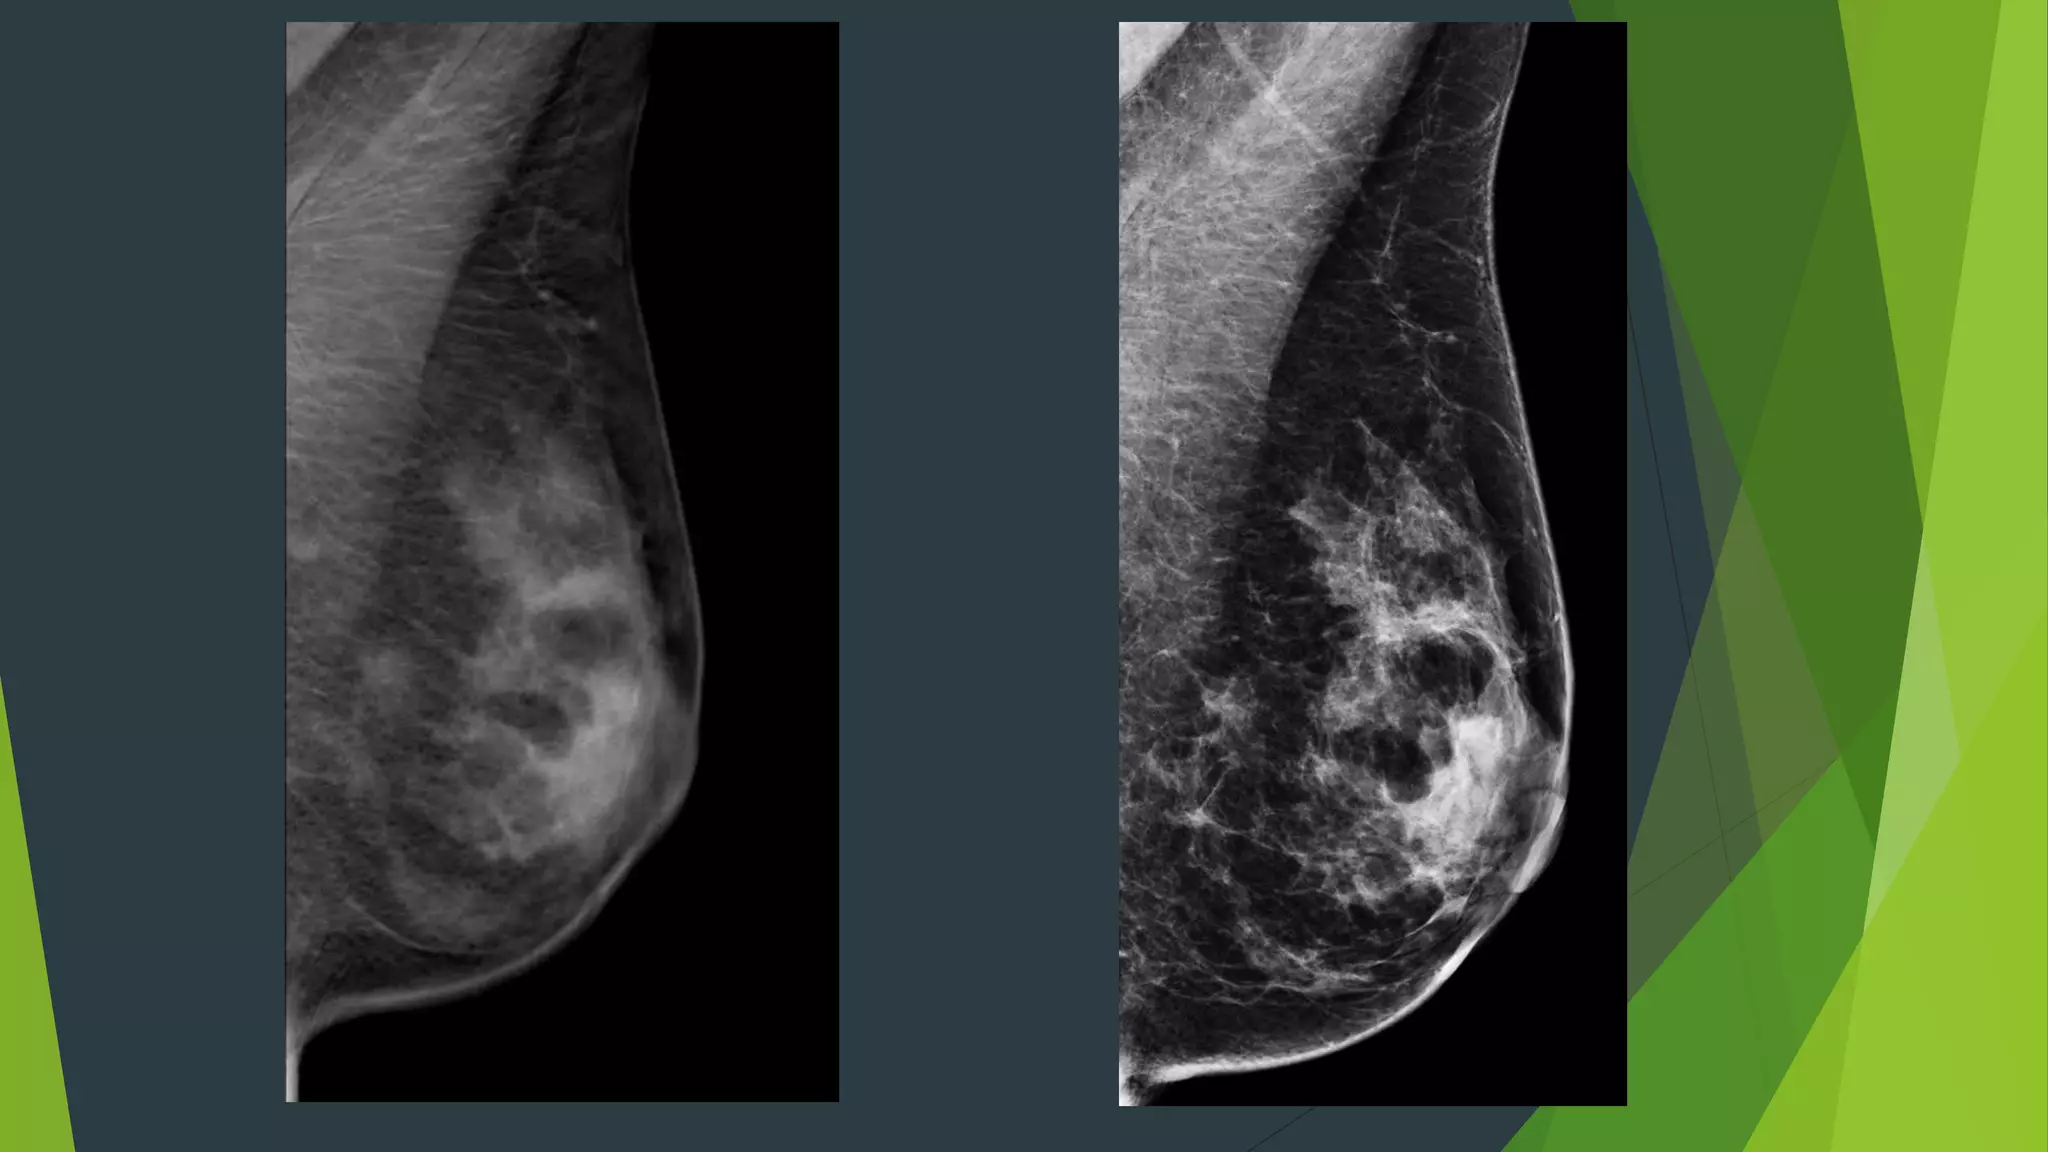

56 year old , screening exam

56 year old, screening exam